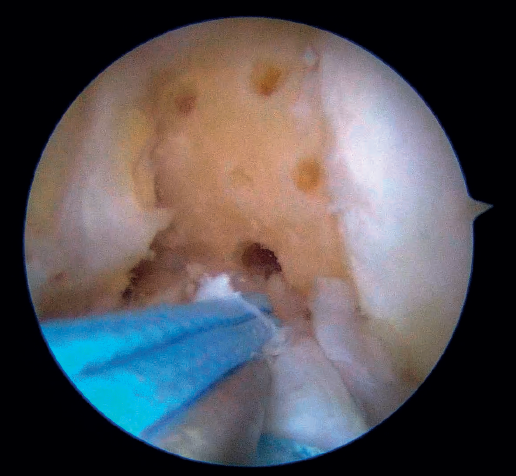

The anteromedial and posterolateral fascicles of the ACL are then identified for suturing separately. Using a suture passer, a closed loop suture is passed through the anteromedial fascicle at its most distal zone, and the loopless extremity is carried alternately (medial to lateral, lateral to medial and so on) to the most proximal zone, usually involving 3 or 4 passes of the suture. The thread may knot on itself during suturing if we are not attentive to it on entry and exit. To solve this problem, we simply undo the knot with retrieval forceps and repeat the step if necessary.

On completion, the thread is retrieved through the accessory anteromedial portal. The process is then repeated, this time with the posterolateral fascicle. To prevent the first thread from breaking with passage of the second thread, it must be ensured that entry and exit in the ligament are very posterior and ideally somewhat proximal to those used for the anteromedial fascicle. Once having reached the most proximal zone after 3 or 4 passes, retrieval is carried out in the same way through the accessory anteromedial portal.

Outside the knee, the threads are loaded into a knotless anchor implant with a tape that will act as anterior reinforcement of the ACL when attached to the tibia. Once the implant has been loaded, it is inserted into the previously prepared site. This step is facilitated when viewing is made from the anteromedial portal, as it affords a better perspective of the zone (Figure 5). Once the implant has been inserted, the suture threads are cut at the level of the condylar wall.